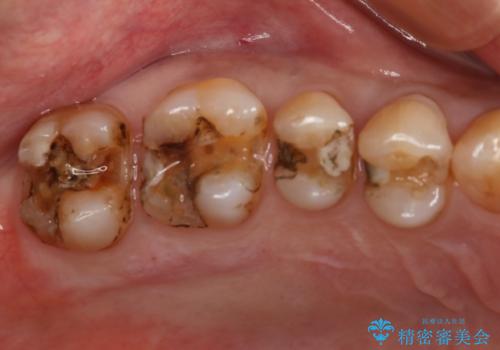

- 虫歯で歯が欠けたことを主訴に来院されました。虫歯の範囲が大きいため被せ物での治療を行うこととなりました。

深い虫歯の治療

虫歯が深く大きくなるほど歯は脆くなっていきます。

虫歯が進行し、神経にまで達している場合には根管治療を行う必要があります。

今回は丁寧に虫歯をとりきることで神経を保存することができました。